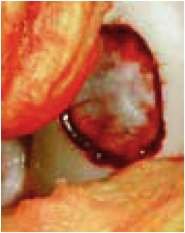

Cette technique réalisée sous arthroscopie ou à ciel ouvert, consiste à prélever des greffes ostéochondrales cylindriques au niveau d’un site donneur non portant puis de les transférer dans des puits receveurs de zones portantes percés au niveau de la zone à greffer (Fig. 4, 5).

Des cylindres de 2,7 à 8,5 mm de diamètre et de 15 à 20 mm de profondeur sont recommandés pour cette opération.

Des ancillaires spécifiques permettent d’encastrer en « press-fit » les cylindres prélevés.

Les études expérimentales ont montré qu’il est nécessaire de remplacer au moins 70% de la surface cartilagineuse manquante pour obtenir un bon résultat.

Les études histologiques aussi bien animales que chez l’homme [21] ont montré qu’environ 10 semaines après l’intervention, la zone transplantée contenait 60 à 70 % de cartilage hyalin et 30 à 40 % de fibro-cartilage, ce dernier s’étant formé à partir de l’os spongieux préalablement avivé.

La morbidité du prélèvement est faible : Hangody et al. [20, 21] rapportent dans une série rétrospective de plus de 1000 greffes en mosaïque, 3 % de morbidité avec quatre infections et 36 hémarthroses. Les contrôles arthroscopiques ont montré, par ailleurs, que les sites donneurs se recouvraient de fibrocartilage et restaient asymptomatiques dans la mesure où il s’agit de zones non portantes.